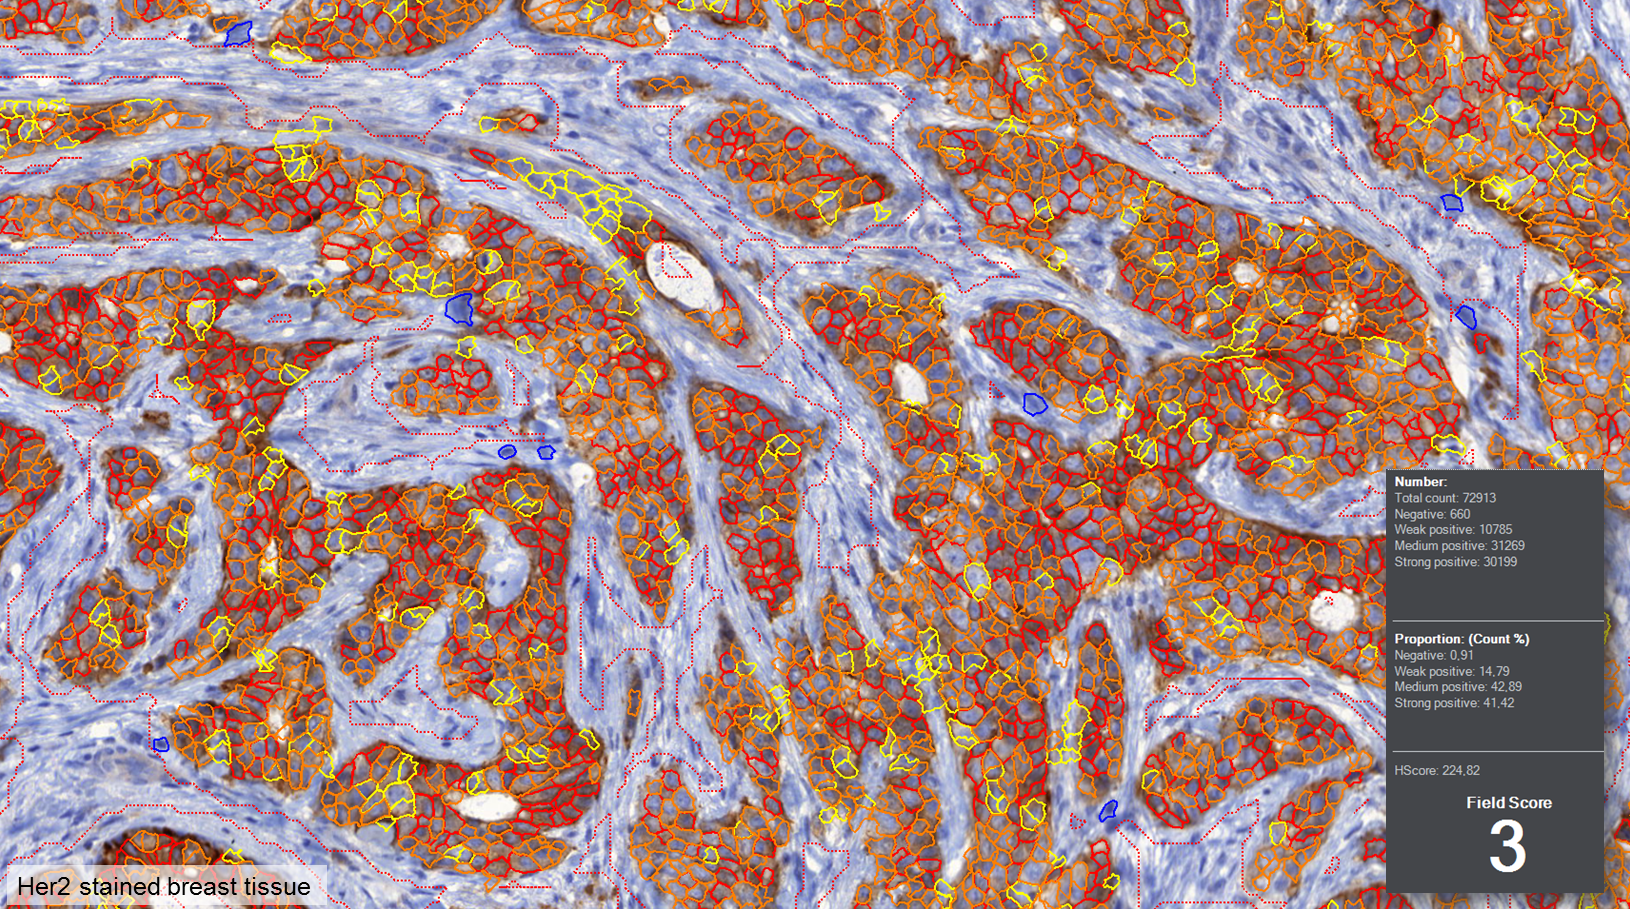

MembraneQuant is a cell membrane detection software application that can be used for the quantification of IHC stained histological samples. This module measures cell morphology and stain density, reports intensity-based core ranges, overall scores and positivity percentages (including H-Score), distinguishing the continuous membrane stain from the moderate stain.

This module has IVD approval for the quantification of Her2 expression in breast tissue samples.